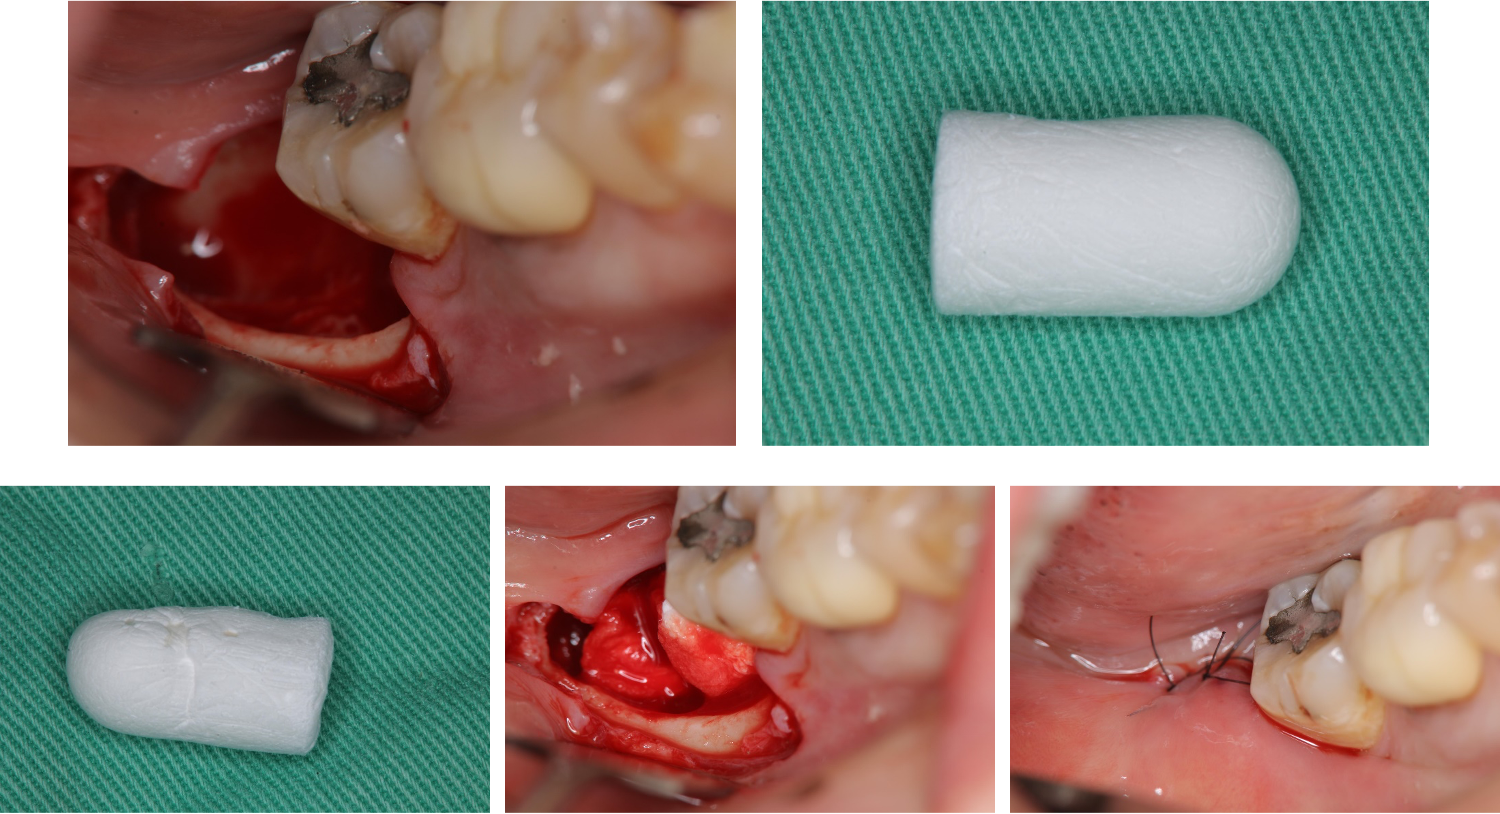

以手機削骨,阻生齒分割,再以拔牙挺等拔除阻生齒,並縫合之

使用骨質增生膠原蛋白,來處理拔牙後的傷口。此材料適用的範圍不僅用於拔牙後傷口,所有顎骨中的病灶於手術後皆建議使用。

骨質增生膠原蛋白優點:

1 、止血效果:特殊生物材料,能立即止血,且無血塊脫落之困擾。

2、減痛效果:加速傷口癒合,有效減輕疼痛

3 、預防效果:健全牙周組織,避免鄰近牙齒產生牙周病及乾性齒槽炎